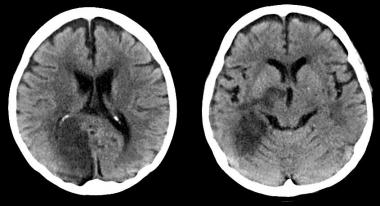

ACV isquémico pequeño: ¿demasiado bueno para tratarlo?

Según un estudio observacional, los pacientes con ictus isquémico y lesiones pequeñas en la tomografía computarizada de perfusión podrían no beneficiarse con la trombolisis. Annals of Neurology, agosto de 2016